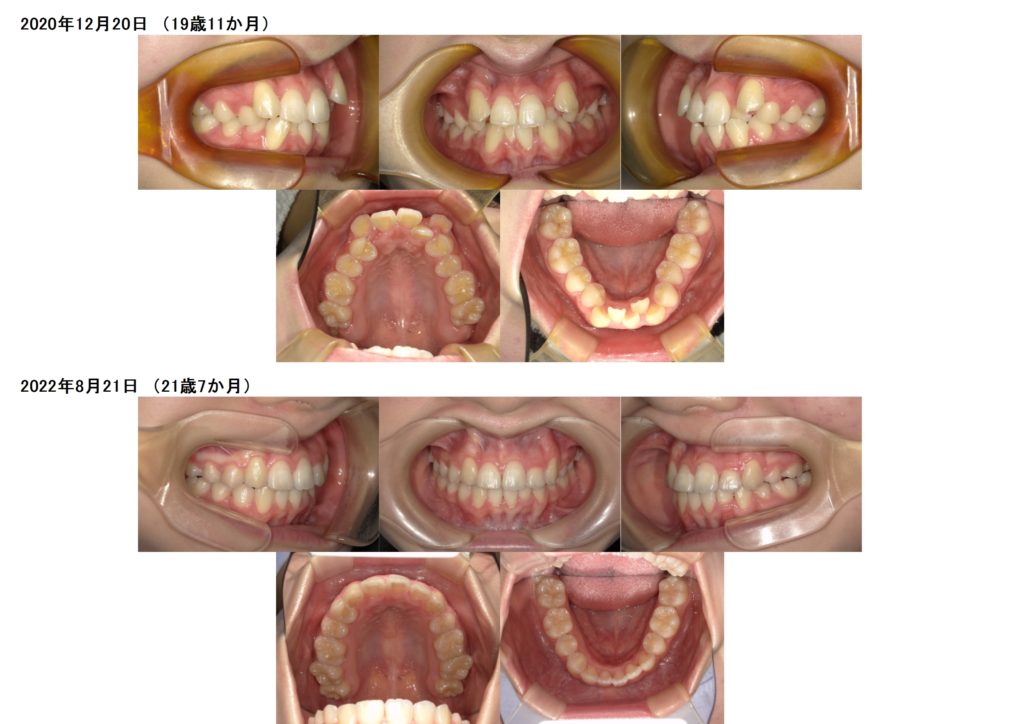

欠損歯がある方の治療例です☆

左側の前歯2番目の上下の歯が欠損です。

とってもキレイに歯並び、噛み合わせが整いました。

患者様の協力があってこそ、治療も早く終了します。

このまま、保定期間に入りリテーナーを使用していただきますが、キレイな歯並びをキープするためにとっても大事な期間でもあります。

今まで磨きづらかった歯ブラシも、装置が外れ歯並びも整ったので磨きやすくなったと思います。